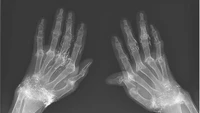

Kejadian tersebut bukan yang pertama, dalam sebuah studi kasus lain, wanita 58 tahun di Korea Selatan melakukan prosedur yang sama di pergelangan tangan. Kondisi artritis reumatoid yang diidapnya justru semakin parah, karena tidak segera mengonsumsi obat anti-rheumatoid dan terlalu lama mengandalkan metode alternatif. (Foto: The New England Journal of Medicine)